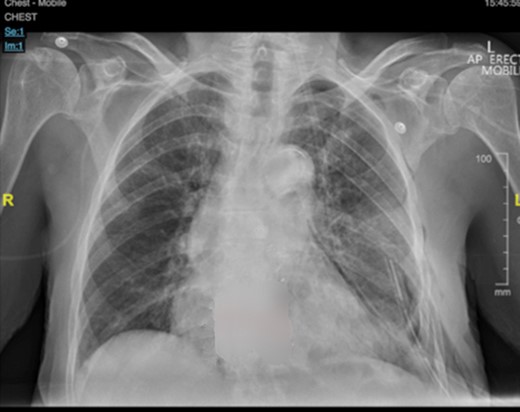

A 92-year-old, previously independent female presented acutely with severe resting dyspnoea, exercise tolerance of less than fifty metres—limited by dyspnoea and presyncope, orthopnoea, peripheral oedema and early satiety. Complete whiteout of left mid-to-lower zones with accompanying mediastinal shift was seen on initial chest X-ray (Fig 1b). CT chest performed in view of these findings demonstrated a giant (130 × 133 × 147 mm) posterior mediastinal mass arising from the left T10/T11 foramina, and causing significant cardiac displacement and complete collapse of left lower lobe and lingula (Fig 1b). Ventilation-perfusion scan showed a matched defect affecting the entire lower lobe and lingula. Percutaneous biopsy of the mass demonstrated a schwannoma (Fig 2).

The patient was extubated postoperatively and transferred to the ward. She recovered well, and began mobilizing on postoperative day 1. The chest drain was removed on postoperative day 2 after complete lung re-expansion (Fig 5). Paravertebral catheter was removed on postoperative day three, and the patient transitioned to oral analgesia without issue. There were no postoperative complications, and the patient was discharged home on postoperative day 4.